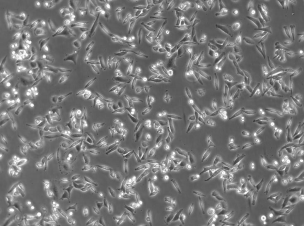

SiHa细胞是建自一个日本病人的外科手术的原位组织样品。电镜观察表明,在SiHa细胞连接处有典型的桥粒,在SiHa细胞胞质中有丰富的张力丝。在裸鼠中,SiHa细胞能形成低分化的表皮样癌(Ⅲ级);SiHa细胞中,癌基因PRB和p53阳性。

细胞形态 上皮细胞样

生长特性 贴壁生长